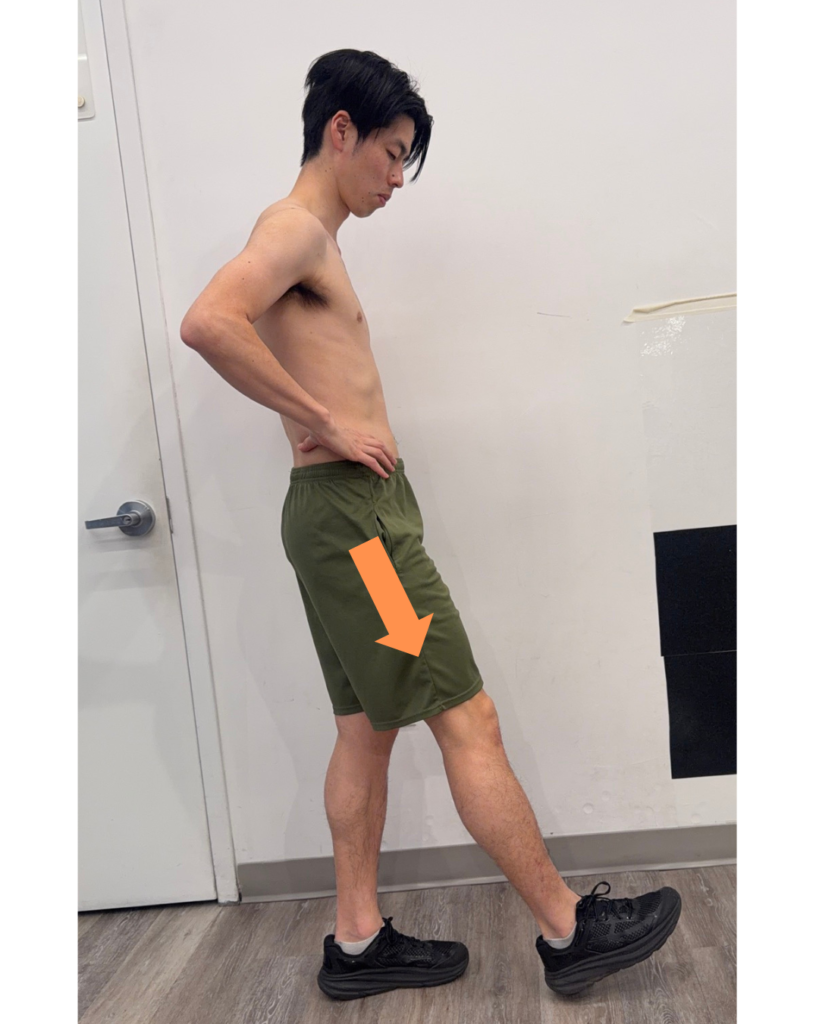

2. Anterior Depression (Initial Contact)

Anterior depression occurs when the pelvis moves forward and downward as the foot contacts the ground.

Role:

- Absorbs impact

- Provides controlled weight acceptance

- Helps distribute forces through the kinetic chain

Muscular connection: eccentric contraction of Quadratus lumborum, other trunk muscle control

Dysfunction:

- Poor control can lead to excessive impact forces at initial contact

- May contribute to conditions such as:

- Heel pain

- Knee pain

- Increased stress through the lower extremity

(poor shock absorption)

3. Anterior Depression Exercise: “Basking Seal”

Goal: Improve control during initial contact

How to perform:

- Lie on your side with hips and knees at 90/90, lower legs off the table

- Slowly rotate hips down to the floor (IR/ER)

- Slow and controlled motion

- May add upper trunk side bending

Focus:

- Improve force absorption

- Reduce excessive loading at heel strike